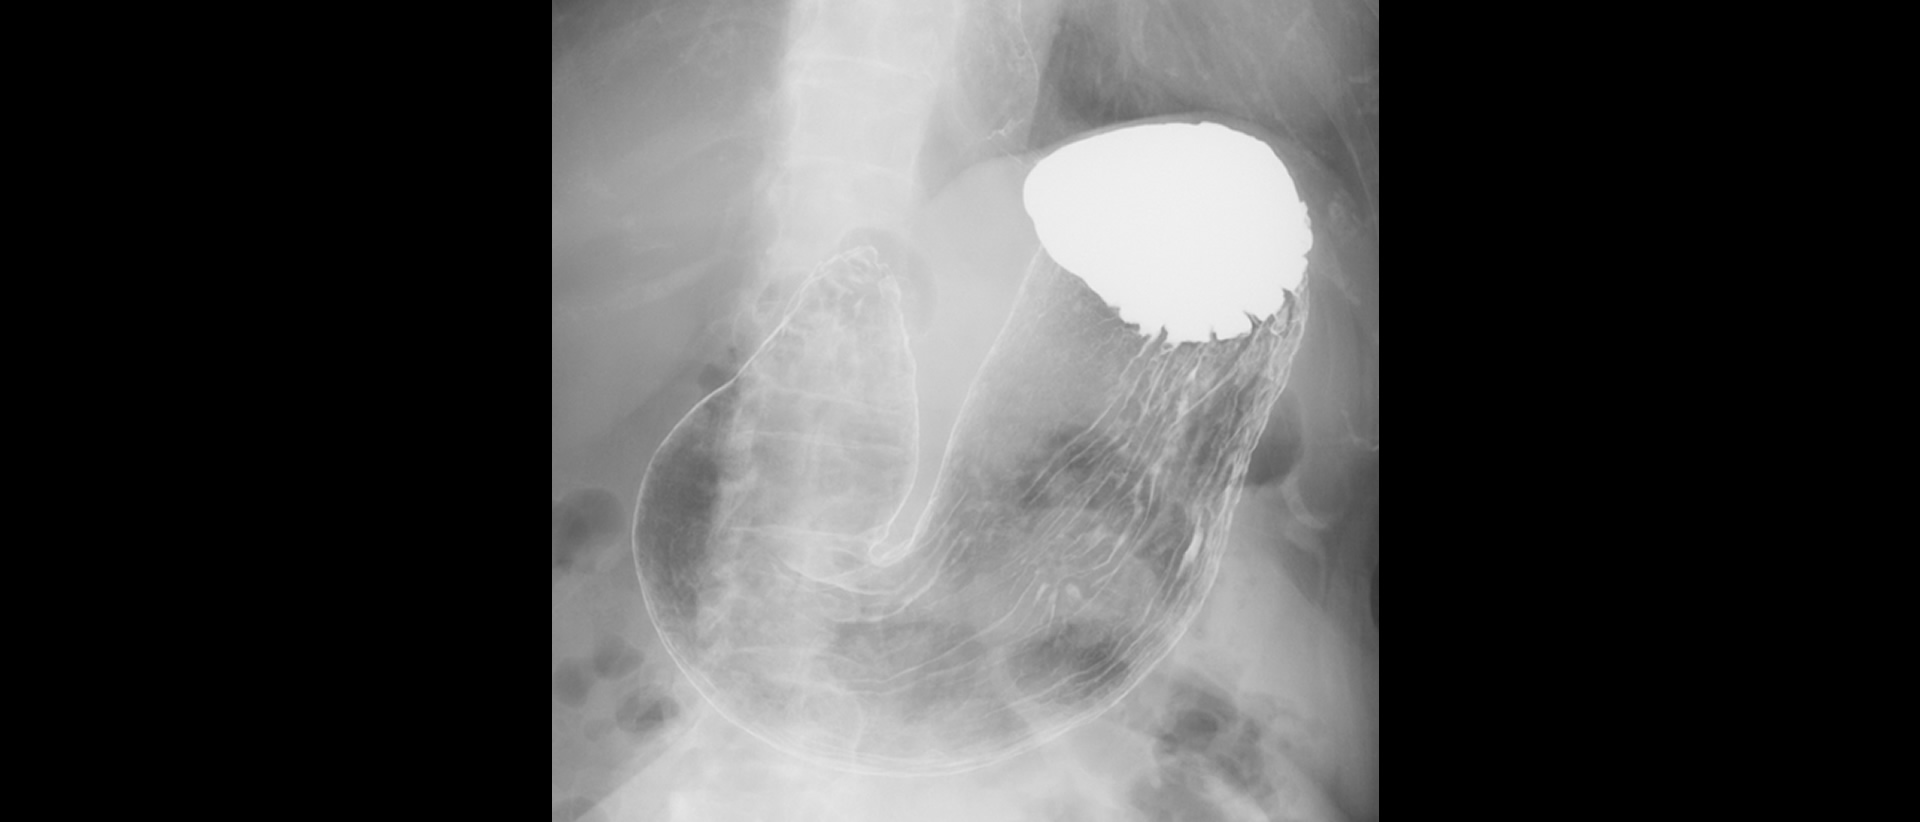

Artículos orientados a Médicos Radiólogos con casos reales de nuestras clínicas